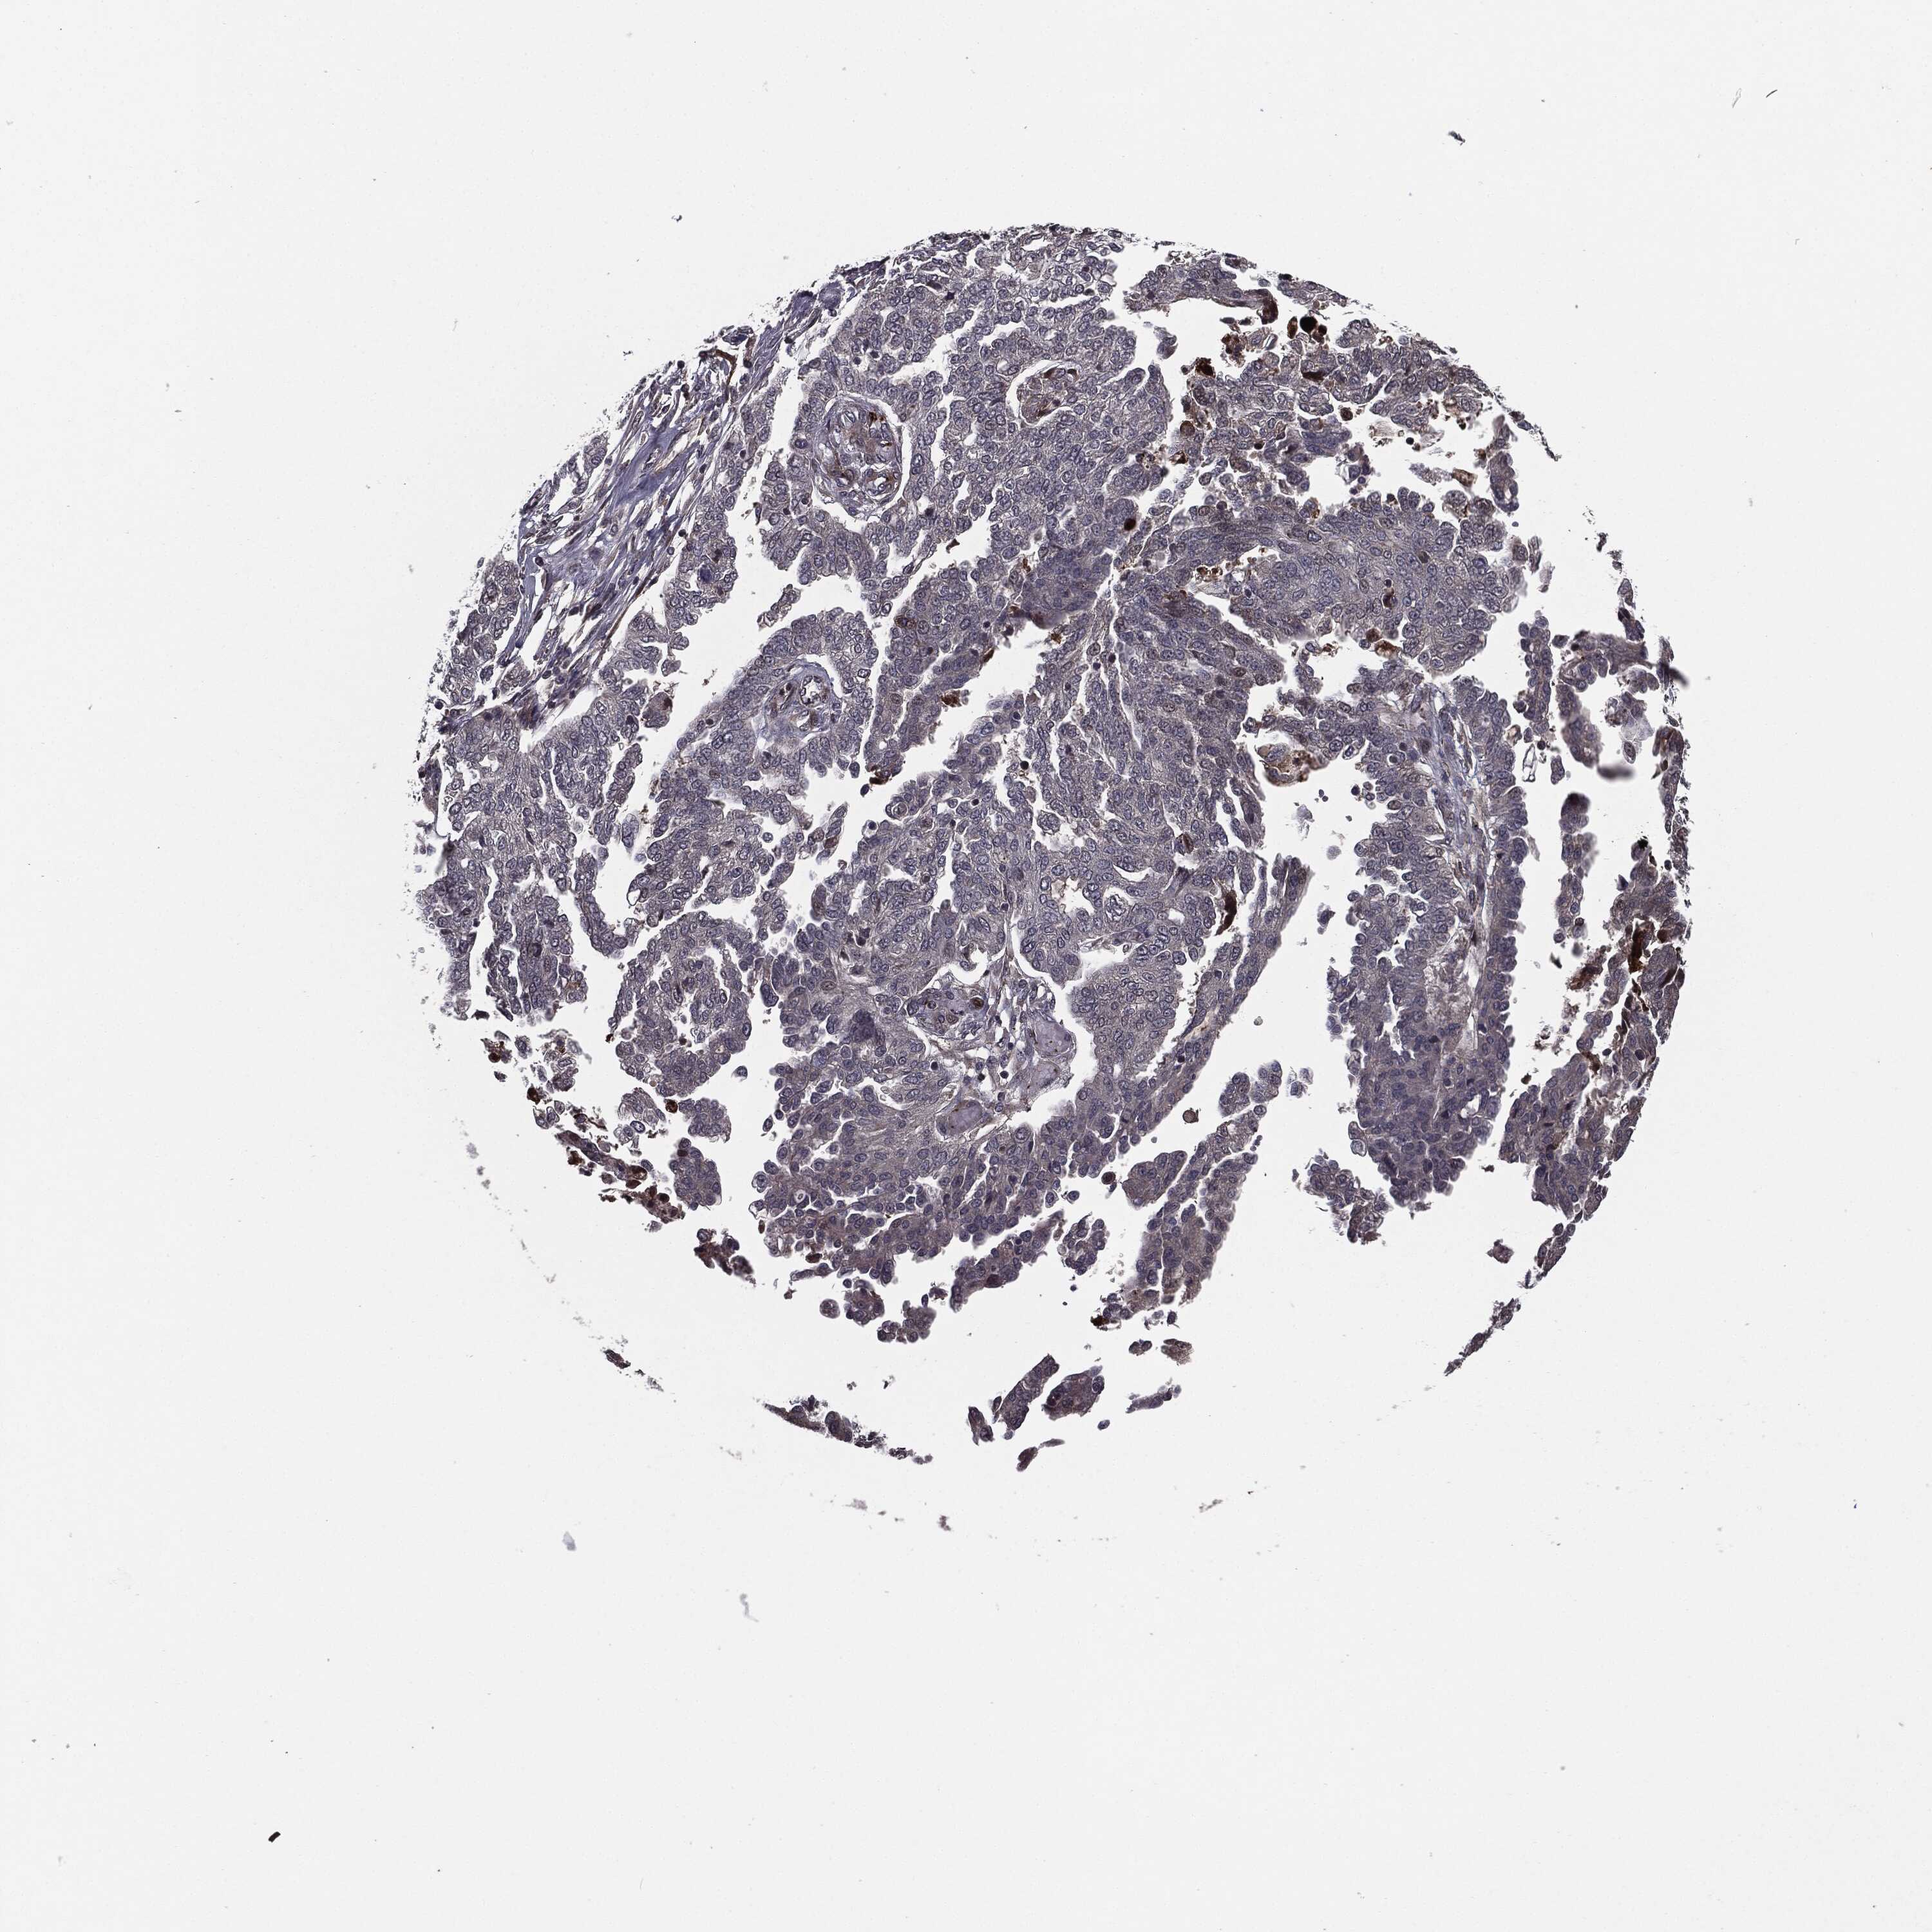

OVARIAN CANCER - Protein expressioni

A mouse-over function shows sample information and annotation data. Click on an image to view it in a full screen mode. Samples can be filtered based on level of antibody staining by selecting one or several of the following categories: high, medium, low and not detected. The assay and annotation is described here.

Note that samples used for immunohistochemistry by the Human Protein Atlas do not correspond to samples in the TCGA dataset.

Antibody stainingi

Antibody staining in the annotated cell types in the current human tissue is reported as not detected, low, medium, or high, based on conventional immunohistochemistry profiling in selected tissues. This score is based on the combination of the staining intensity and fraction of stained cells.

Each image is clickable and will lead to virtual microscopy that enables deeper exploration of all samples and also displays staining intensity scores, fraction scores and subcellular localization as well as patient and tissue information for each sample.

Antibody HPA052606

Antibody HPA077139

Staining

High

Medium

Low

Not detected

Intensity

Strong

Moderate

Weak

Negative

Quantity

>75%

75%-25%

<25%

None

Location

Nuclear

Cytoplasmic/membranous

Cytoplasmic/membranous,nuclear

Cystadenocarcinoma, serous, NOS

Carcinoma, endometroid

Cystadenocarcinoma, mucinous, NOS

Carcinoma, NOS